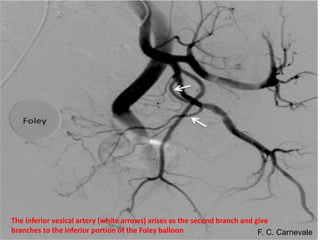

The prostate gland is a pyramid-shaped organ that weighs approximately 20 grams and measures 3x4x2 cm. It has three zones - the peripheral zone (70%), central zone (25%), and transitional zone (5-10%). Prostate cancer develops in the peripheral zone, while benign prostatic hyperplasia (BPH) develops in the transitional zone. The prostate receives its blood supply from various arteries, most commonly the internal pudendal artery (34%). Knowing the detailed arterial anatomy is important for procedures like prostate artery embolization (PAE) to treat conditions like BPH and prostate cancer. Imaging tools like CT angiography and cone beam CT can help the interventional radiologist map the arterial supply before